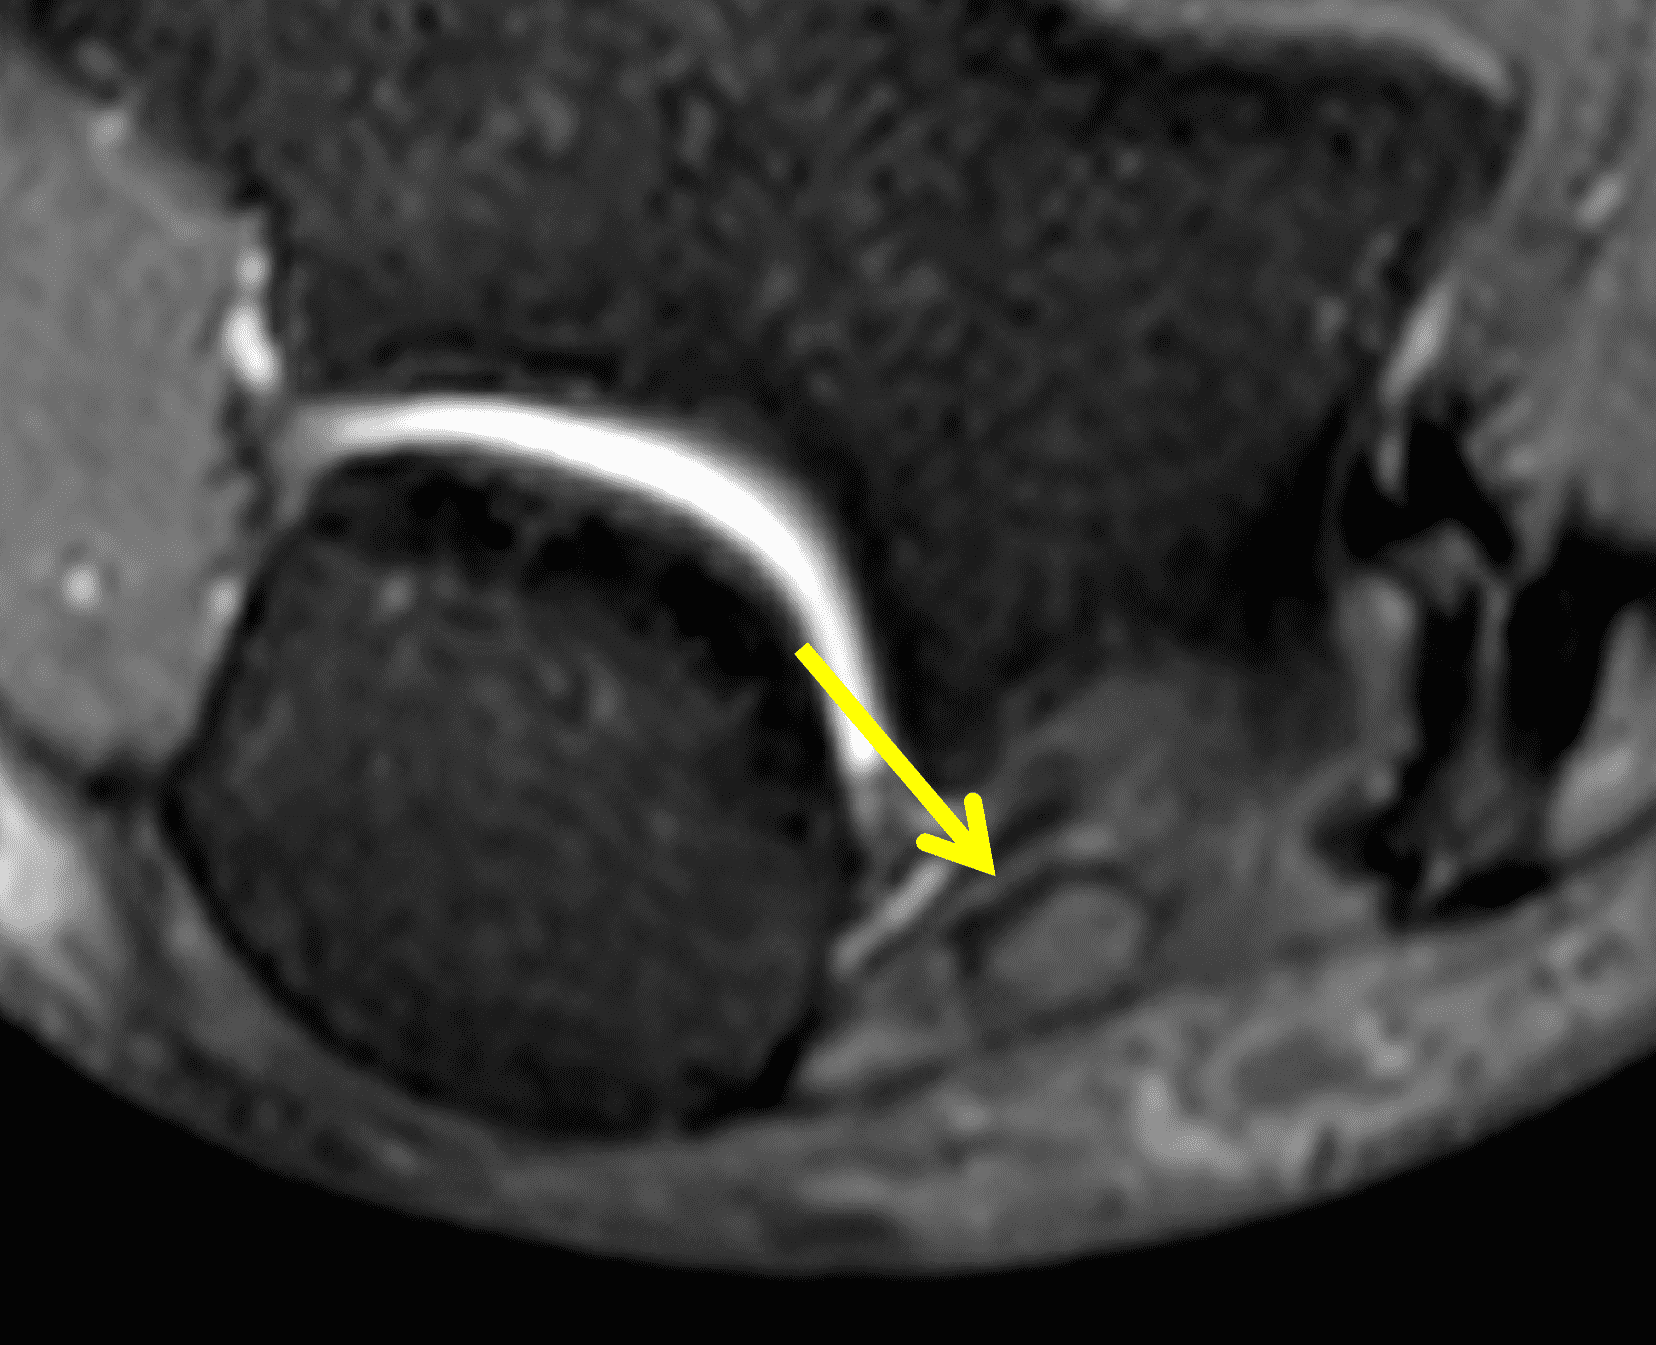

Figure 2: At the level of the cubital tunnel (2A and 2C), identifiable by the thin cubital tunnel retinaculum (yellow arrow), the ulnar nerve (red arrow) is focally enlarged and hyperintense compared to the nerve more distally (2B and 2D), where it lies between the two heads of the flexor carpi ulnaris muscle (asterisks). No soft tissue mass is present.